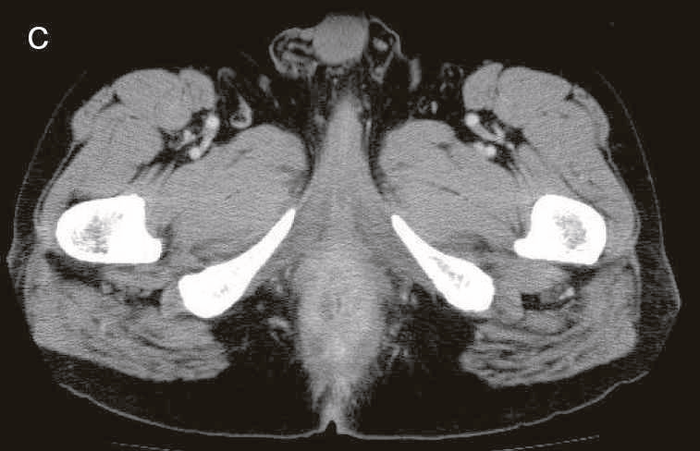

図38 骨盤部MRI

術前の骨盤部MRIでは右側の痔瘻瘻管と,左側の瘻管,周囲のリンパ節腫大を認めた。

明らかな癌を示す所見は不明であった。

精査で施行したCT,MRIで痔瘻癌が疑われた。

診断時のMRIでは直腸下部壁内から周囲にhigh intensity areaが拡がり,右側には痔瘻の瘻管を認めた。high intensity areaは前方で前立腺や陰茎海綿体付近まで広がっていた。

CTではMRIと同様に広範囲のhigh density areaがあり,癌と炎症が波及した領域の区別がつかず右側方領域にリンパ節腫大を認めた。